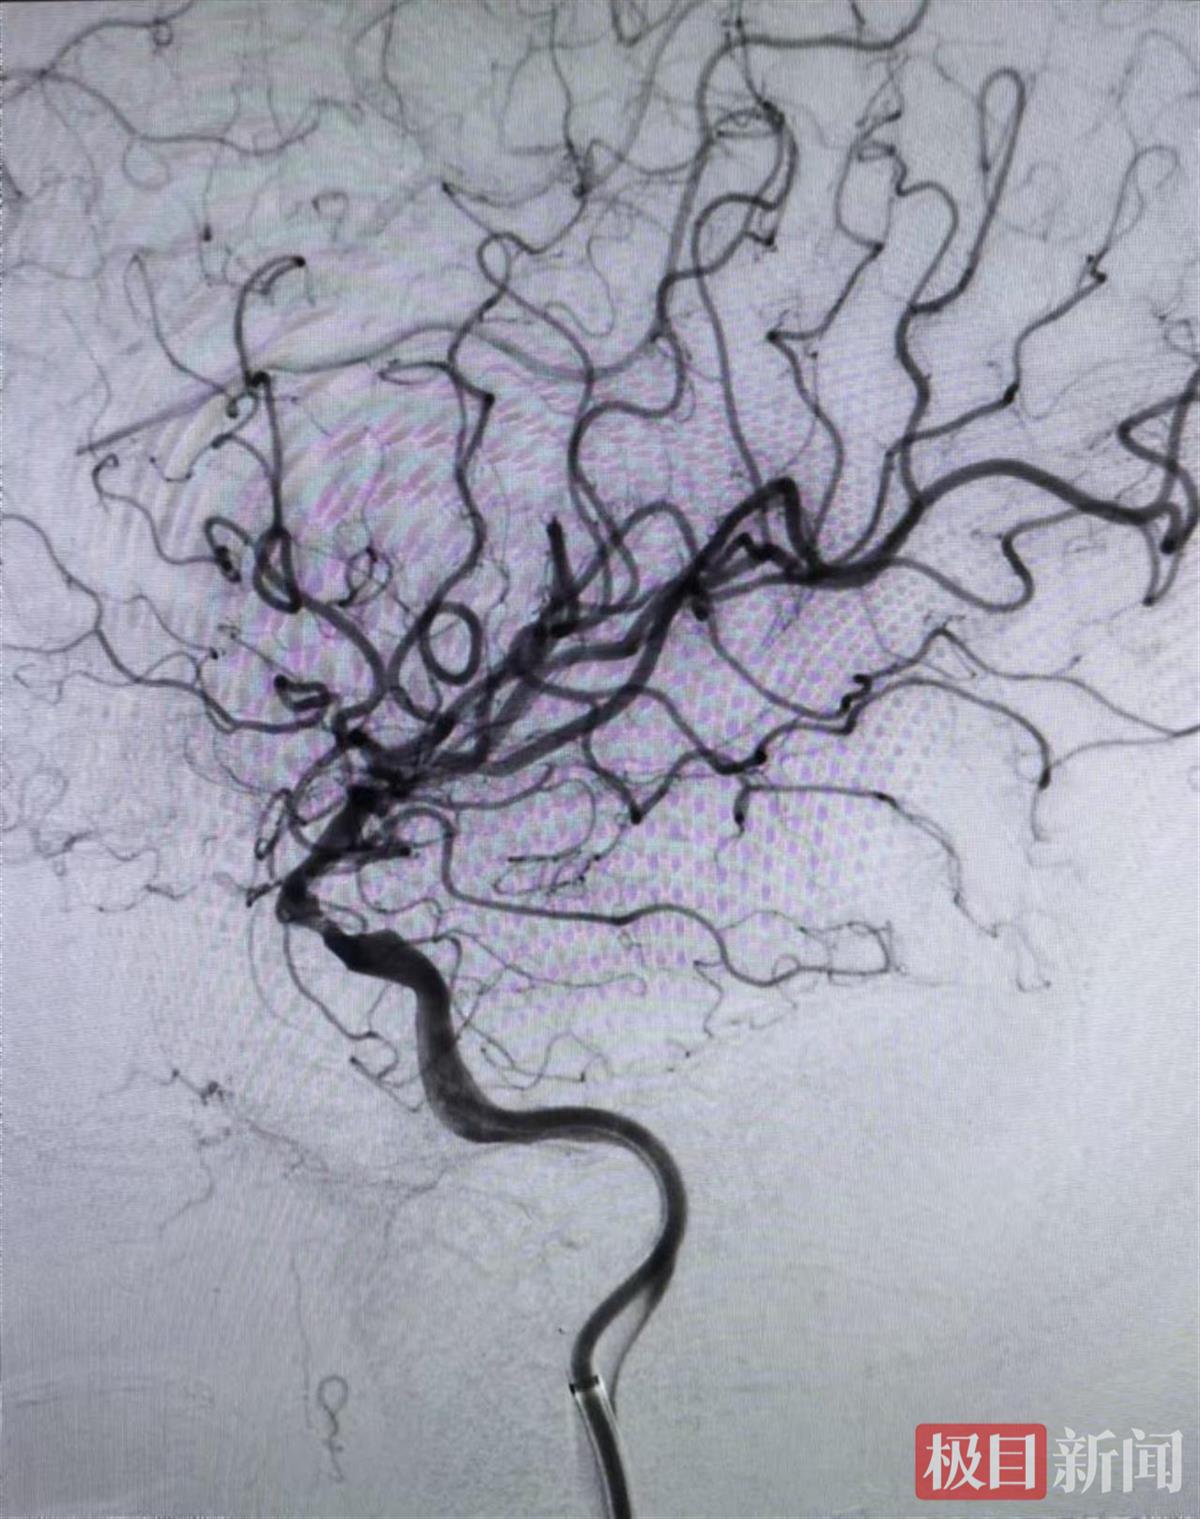

患者取栓后血流通畅

该院神经内科主任黎逢光当机立断,迅速为陈先生制定了一套完备的手术方案。当日下午,黎逢光带领团队为陈先生进行急诊脑血管介入治疗手术,取出闭塞血管内的血栓。术中,医生发现左侧颈内动脉C6段重度狭窄,在进行球囊扩张成形术后,闭塞血管实现再通。术后,陈先生恢复状况良好,右侧肢体肌力和语言功能都基本恢复正常。